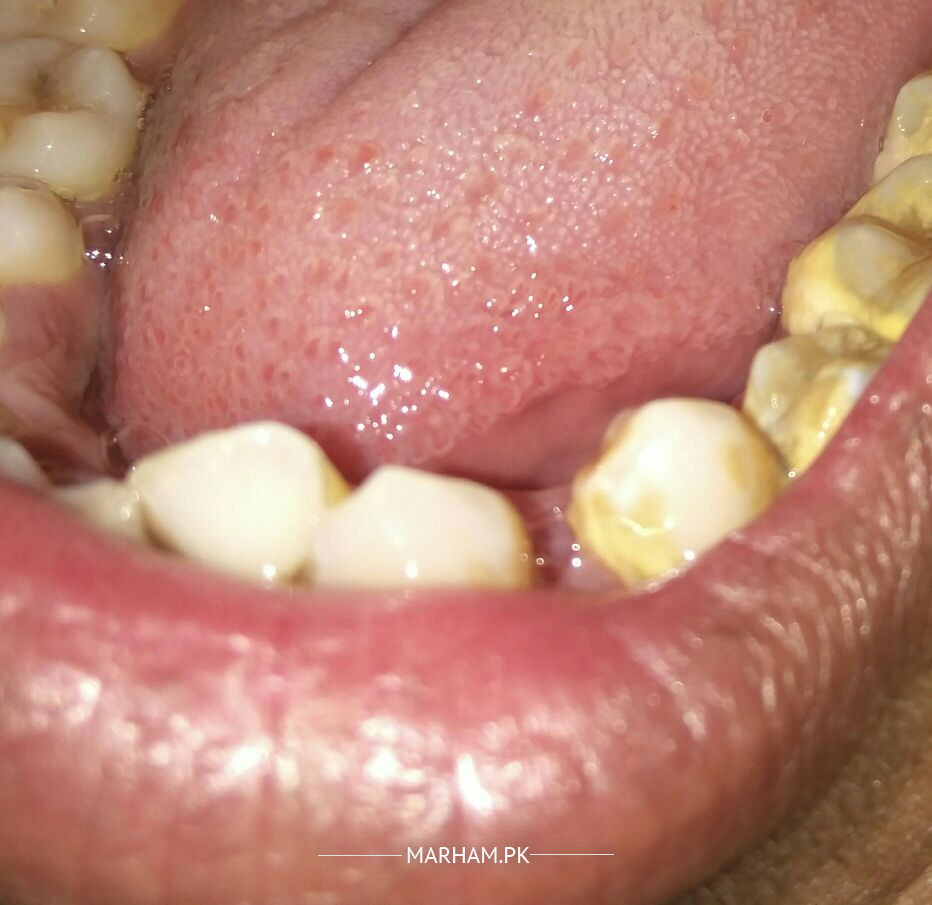

Respected Sir I have recently removed rupturer milk teeth from the dentist. Now kindly see in image that there is space left behind. almost 1 month has been passed since i removed this teeth. When my brush touches its surface it sometimes start bleeding. I have not started eating from this side. Kindly tell me what to do with this space. Is this Ok. There is need to fill it. Will there any be problem if I eat food from this side. I am fearful that if i eated from this side then it would start bleedings. So kindly suggest me what should I do I have to eat from this side

Aoa. It looks like you need improvement in oral hygiene as your brushing technique is improper I guess. Did your dentist suggest any medicines after extraction and did you follow? Visit your nearby dentist for scaling to remove tartar as seen in pics. This will help reduce pain or bleeding. It's difficult to place a new tooth over it but after clinical examination, some solution can be sorted out. You can contact MARHAM for further appointment. Regards

The cause of bleeding is gingivitis.. visit ur nearby dentist for scaling as heavy calculus deposit on ur teeth that causes the gum to inflammed and bleed on brushing

the problem i can see in this pic is the calculus/tartar/ yellow material seen on your tooth due to which your gums are bleeding. you need to do scaling so that your gums health improves and bleeding stops